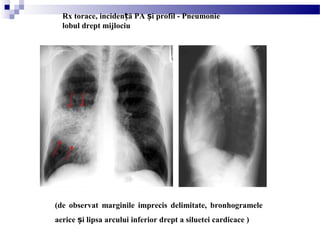

(de observat marginile imprecis delimitate, bronhogramele

aerice i lipsa arcului inferior drept a siluetei cardicace )ș

Rx torace, inciden ă PA i profil - Pneumonieț ș

lobul drept mijlociu